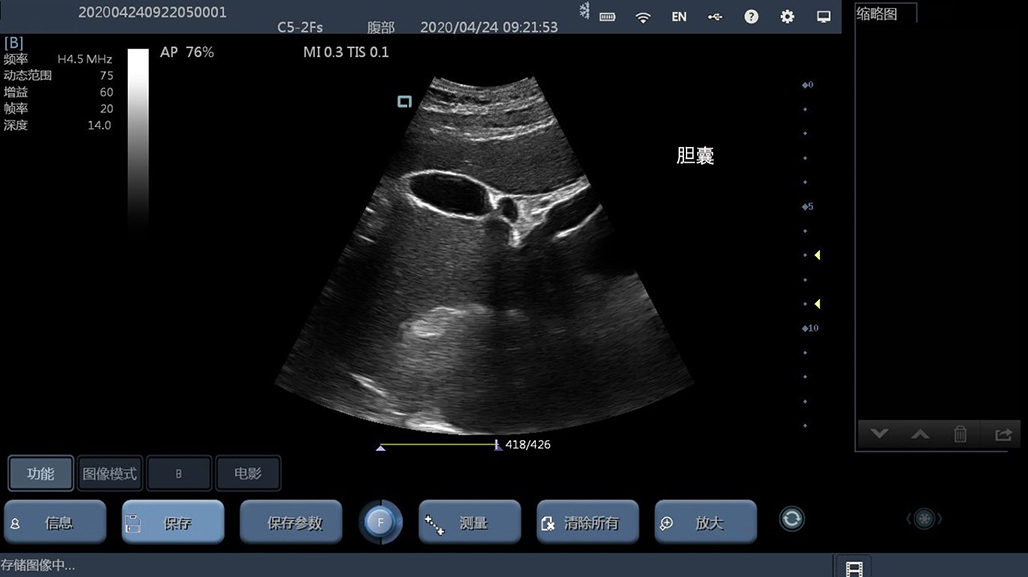

• 大凸

腹部

肾脏

妇科产科

心脏

肺等